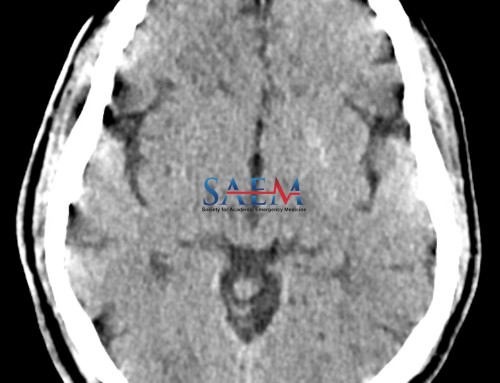

When do you need a head CT before an LP?

The LP is useful for diagnosing meningitis, subarachnoid hemorrhage, and other auto-immune or inflammatory disorders. However, the LP will obviously not be appropriate for diagnosing a brain mass, a stroke, or a skull fracture. In general, when you are suspecting any of these based on the history and physical, the patient should have appropriate imaging first. Here is a quick mnemonic for patients in whom you should consider a CT before an LP, with the acronym “TAP AS IF”.

If the patient has an obvious source of their symptoms on CT, such as a mass, hematoma, fracture, or abscess, then the LP can be deferred if the findings explain the clinical history. If they have signs of midline shift, obstructive hydrocephalus, or cerebral edema, then an LP should be avoided.